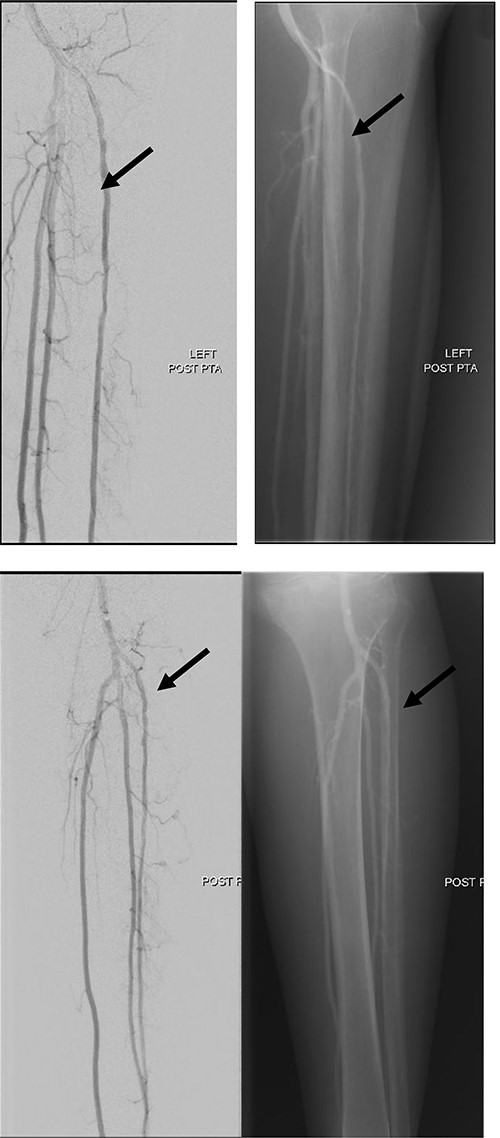

She subsequently underwent left lower limb angioplasty and stenting of the ATA with good results (Figs 4–7) and was started on antiplatelet therapy. Following successful angioplasty, she underwent early wound coverage procedure. A medially based rotation advancement flap was raised for coverage of wound defect. Patient completed 2 weeks course of broad-spectrum antibiotics post-operatively. Patient’s flap was stable and she was allowed partial weight bear over her left lower limb with Darco shoes at post-operative Day 12.

Left lower limb diagnostic angiogram showing occlusion of the ATA with poor flow (arrow).

Angiogram of left distal leg and foot showing poor flow of the distal ATA and dorsalis pedis artery (arrow).

Good arterial flow of the ATA (arrow) after successful angioplasty and stenting.

Arterial flow noted at distal ATA and dorsalis pedis artery (arrow) after successful angioplasty and stenting.